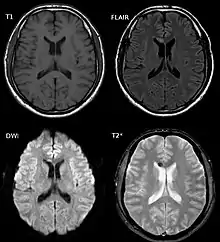

| Two MRI images of a patient with diffuse axonal injury resulting from trauma, at 1.5 tesla field strength. Left: conventional gradient recalled echo (GRE). Right: Susceptibility weighted image (SWI). | |

DAI is difficult to detect since it does not show up well on CT scans or with other macroscopic imaging techniques, though it shows up microscopically.[9] However, there are characteristics typical of DAI that may or may not show up on a CT scan. Diffuse injury has more microscopic injury than macroscopic injury and is difficult to detect with CT and MRI, but its presence can be inferred when small bleeds are visible in the corpus callosum or the cerebral cortex.[34] MRI is more useful than CT for detecting characteristics of diffuse axonal injury in the subacute and chronic time frames.[35] Newer studies such as Diffusion Tensor Imaging are able to demonstrate the degree of white matter fiber tract injury even when the standard MRI is negative. Since axonal damage in DAI is largely a result of secondary biochemical cascades, it has a delayed onset, so a person with DAI who initially appears well may deteriorate later. Thus injury is frequently more severe than is realized, and medical professionals should suspect DAI in any patients whose CT scans appear normal but who have symptoms like unconsciousness.[9]